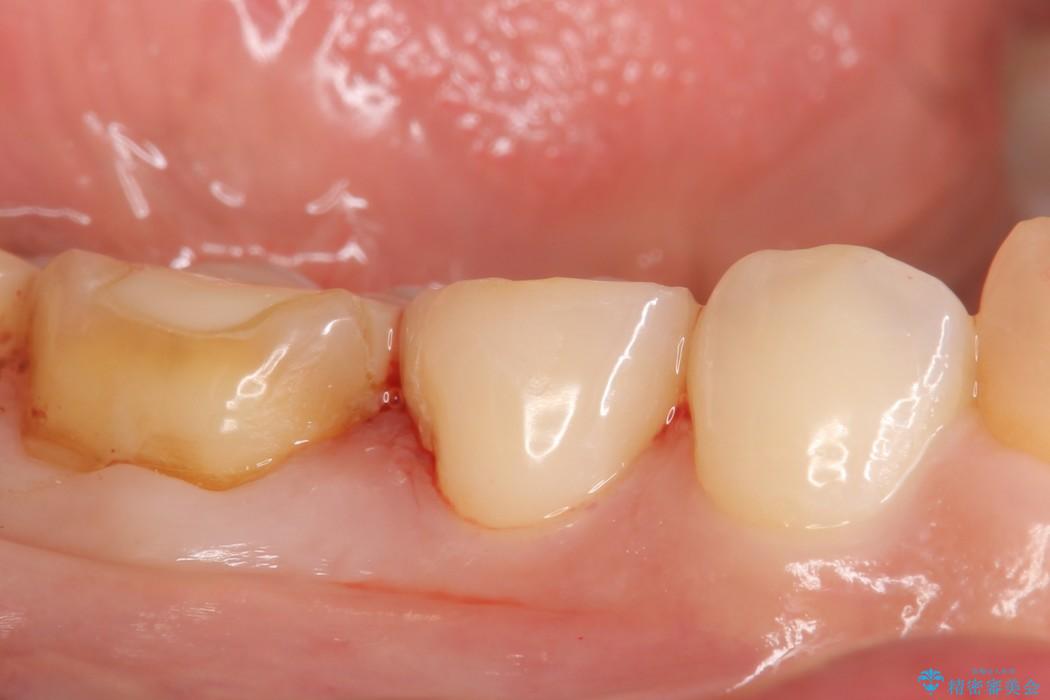

ぱっと見ただけでは特に問題ないように見えますが、レントゲンをよく確認すると詰め物と歯の間に隙間がはっきりと確認ができます。

隙間が発生しているインレー(詰め物)

治療完了した歯でも、時間の経過や力的作用によってセメントが変性したり、隙間が空くことによって詰め物の下に虫歯が発生したりすることがあります。